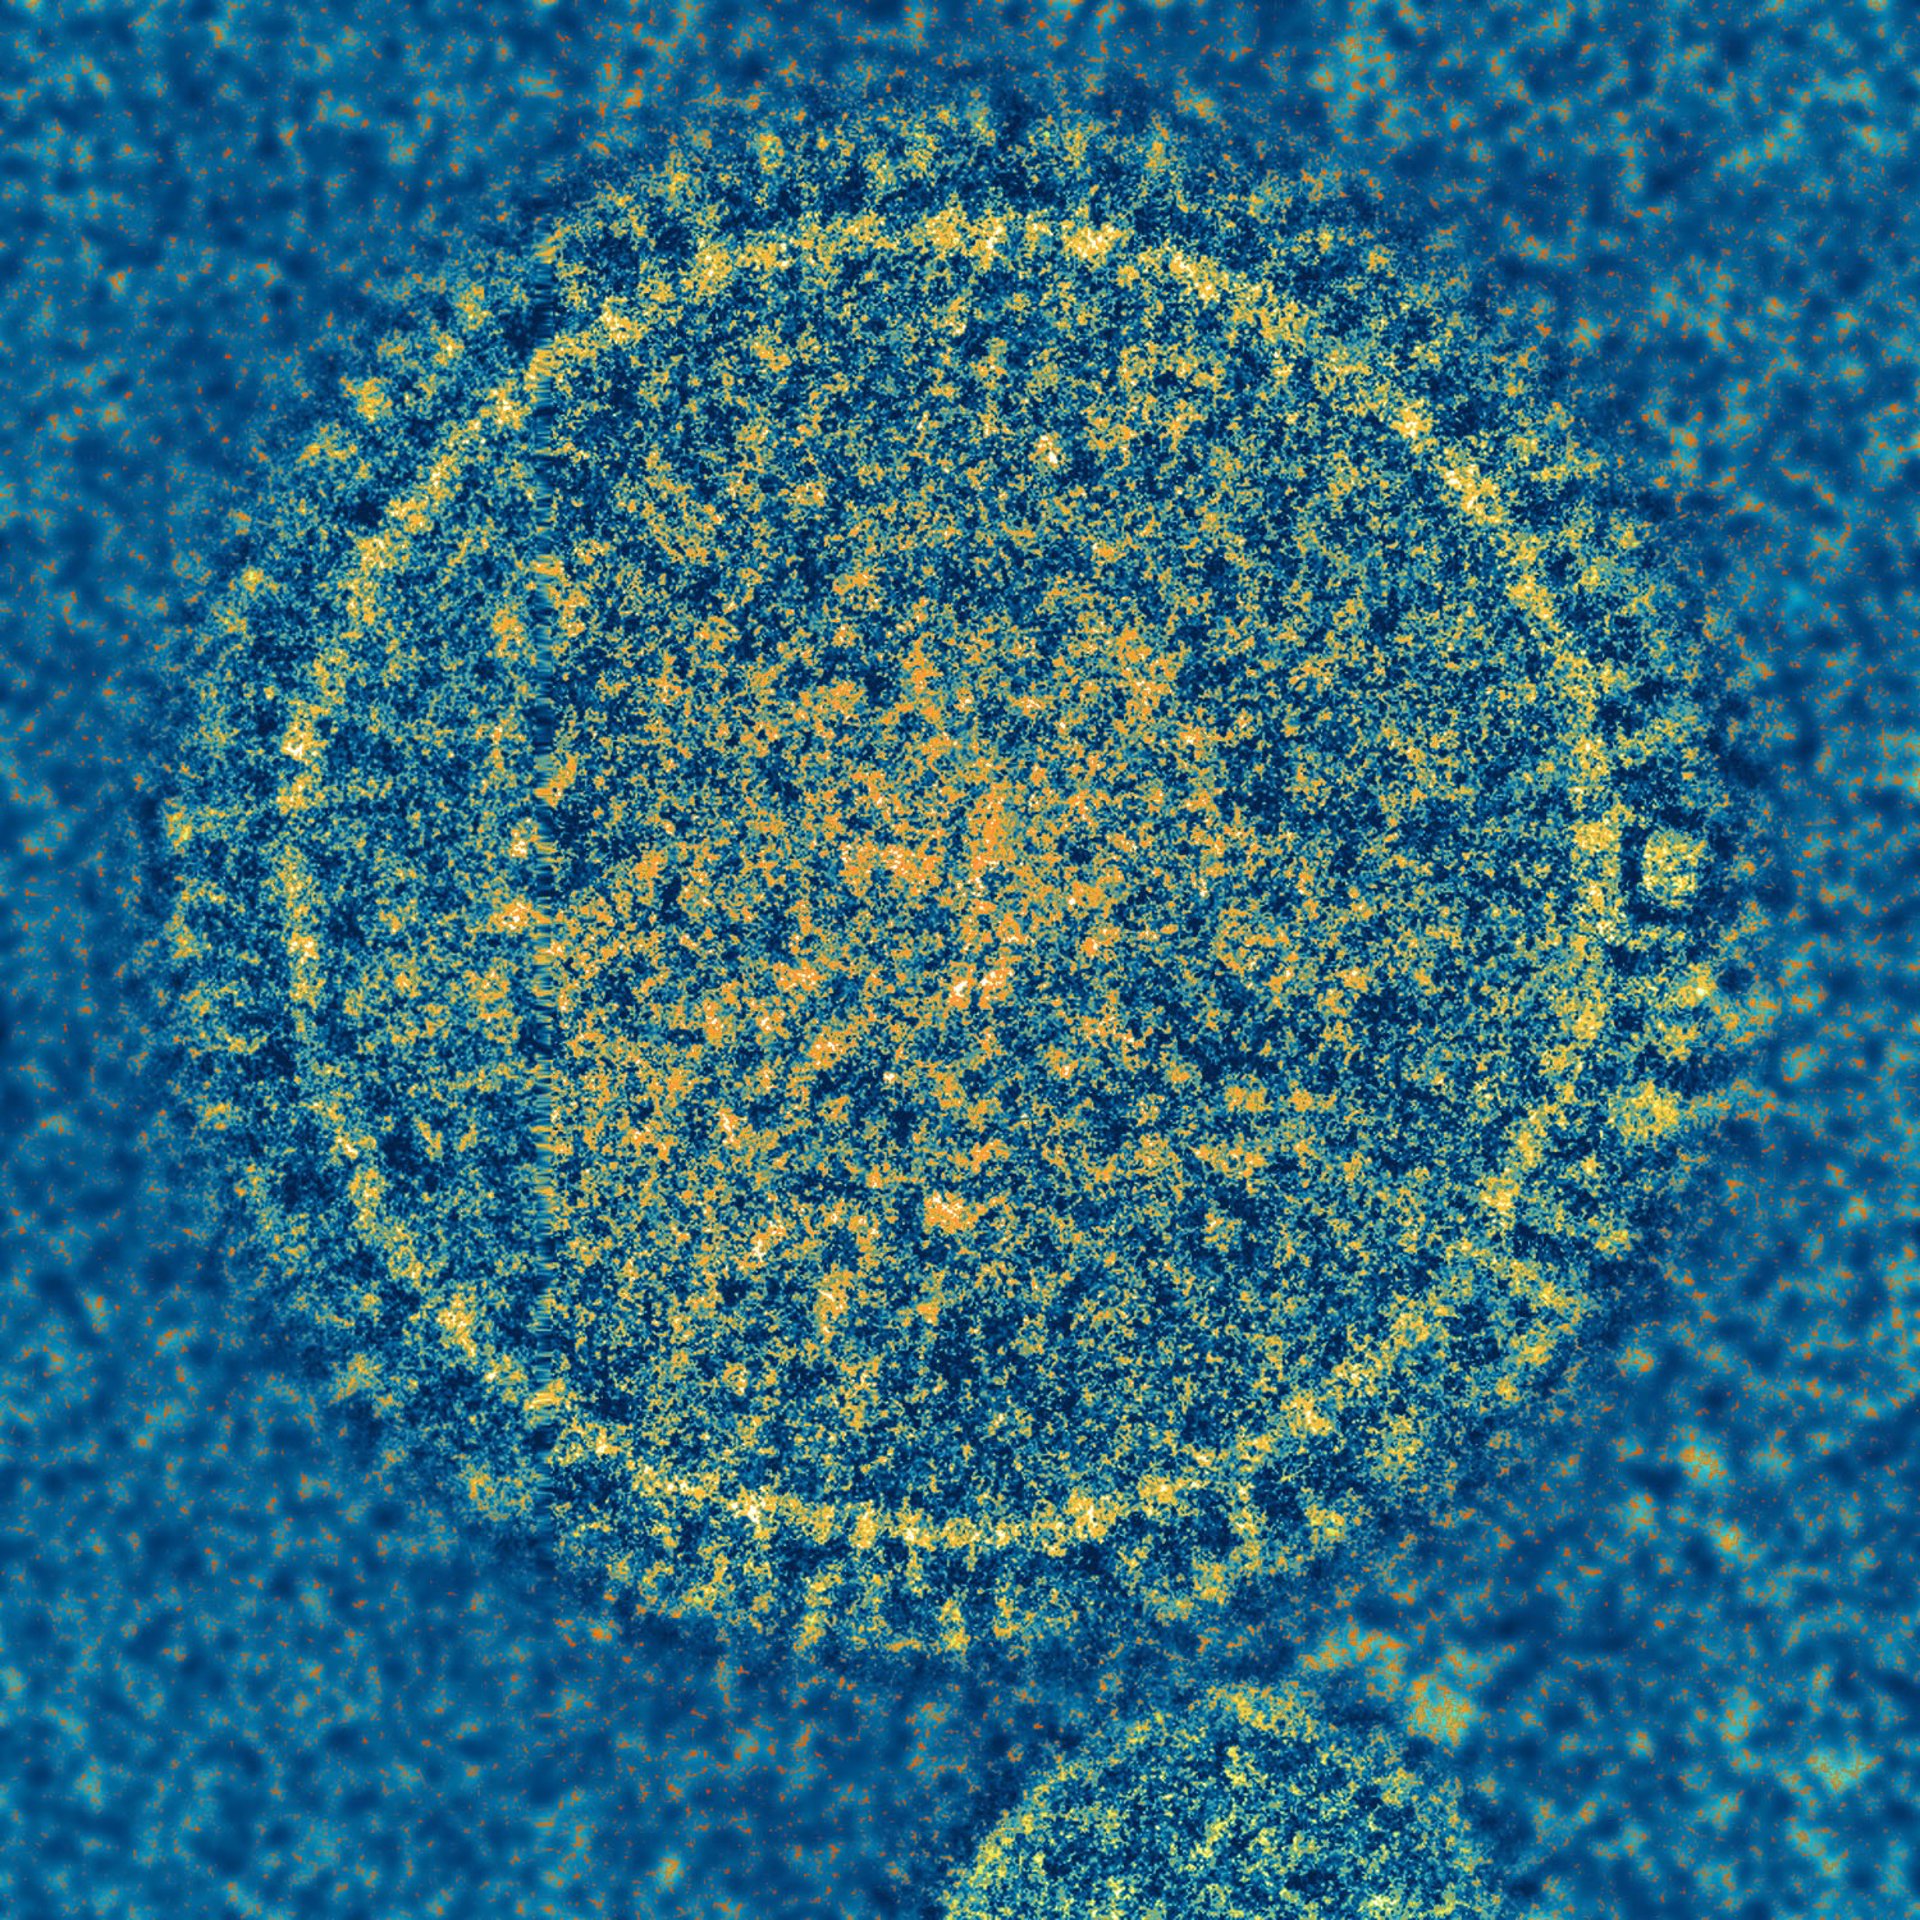

Las respuestas inmunitarias sugieren por qué algunos niños contraen una infecció

Las respuestas inmunitarias sugieren por qué algunos niños contraen una infecció - NIAID - Archivo

Al estudiar una cohorte de 190 niños, un equipo de investigación descubrió pistas importantes que podrían ayudar a explicar por qué algunos niños con infecciones por el virus sincitial respiratorio (VSR) tienen casos leves, mientras que otros tienen enfermedades más graves y requieren hospitalización.

Los resultados, que publican en la revista 'Science Translational Medicine', identifican características importantes en la respuesta inmune al VRS y podrían informar el desarrollo de una vacuna históricamente esquiva para la enfermedad.

El VSR es una enfermedad común en niños y representa la causa más frecuente de hospitalización en recién nacidos en los países desarrollados, aunque a menudo solo causa síntomas leves.

Los investigadores también sospechan que los casos más graves están vinculados a respuestas anormales del sistema inmune. Para investigar, el investigador Santtu Heinonen y sus colegas de la Universidad de Helsinki, compararon las firmas inmunes en muestras de sangre tomadas de un grupo de 190 niños pequeños, incluidos 125 niños con infecciones por VRS y 65 controles sanos.